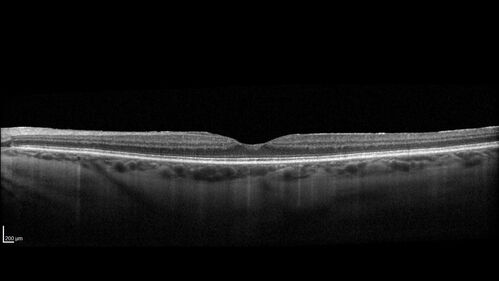

Lamellar Macular Hole and Good Vision

67 year old woman with good vision and floaters - VA 20/32 OD, 20/23 OS